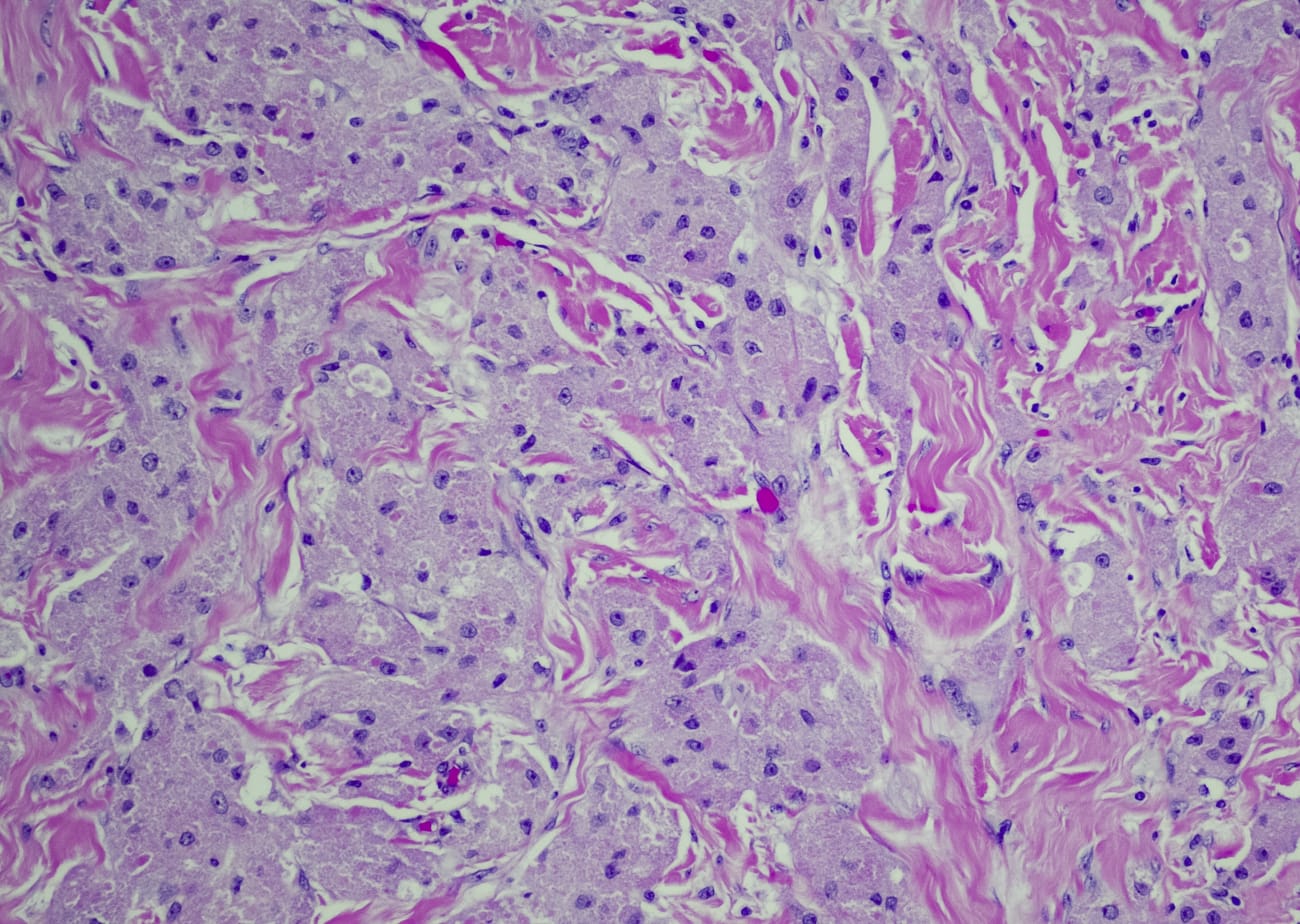

When the complete pathology report came back the following week, it showed that the cancer was the rare granulosa cell tumor, and, also, that it had not spread to the patient’s lymph nodes or other organs.

While the granulosa cell tumor hadn’t visibly ruptured or spread, the final pathology report noted that there were microscopic cells noted in the washings, making the cancer Stage 1C, for which chemotherapy is recommended. The patient completed six cycles of chemo with Bruce Kressel, a medical oncologist at Johns Hopkins Kimmel Cancer Center at Sibley. Afterward, the patient had no evidence of disease, and now sees Staples every three months for a pelvic exam and blood work.